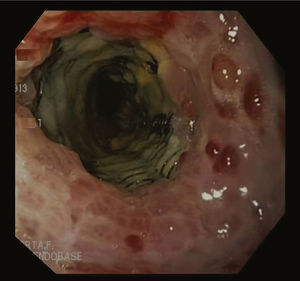

Caso clínicoMujer de 49 años con obesidad mórbida en quien se realizó una GV laparoscópica, sin incidencias postoperatorias. Dos meses después de la cirugía presentó fiebre intermitente durante una última semana, sin otra sintomatología asociada. Las pruebas revelaron leucocitosis y PCR elevada. Un TC abdominal mostró un absceso en la región subhepática. Se intentó drenaje percutáneo del absceso; pero, durante el procedimiento la paciente se inestabilizó y presentó hematemesis y signos de shock séptico, por lo que se la trasladó a quirófano para realizar una laparotomía exploradora. Se drenó el absceso a lo largo de la línea de grapas sin poder objetivar fuga alguna, así que se realizó una endoscopia intraoperatoria que evidenció el punto de disrupción. Con este hallazgo, se colocó un stent de metal parcialmente cubierto Ultraflex® (Boston Scientific®) 12cm de longitud y 18mm de diámetro. Cuatro semanas más tarde, se citó para retirar la prótesis, pero el procedimiento no resultó puesto que ambos extremos del stent estaban cubiertos por tejido hiperplásico de manipulación compleja por el riesgo de perforación esofágica (fig. 1). Por tanto, se aplicó la técnica del «stent in stent» colocando de forma coaxial una nueva prótesis totalmente recubierta Polyflex® (Boston Scientific®) con el objetivo de obtener la necrosis del tejido hiperplásico. A los 15 días, una nueva endoscopia reveló que el primer stent se había separado de la pared y se procedió a extraer ambas prótesis (fig. 2). La paciente evolucionó favorablemente y recibió el alta 3 días después.